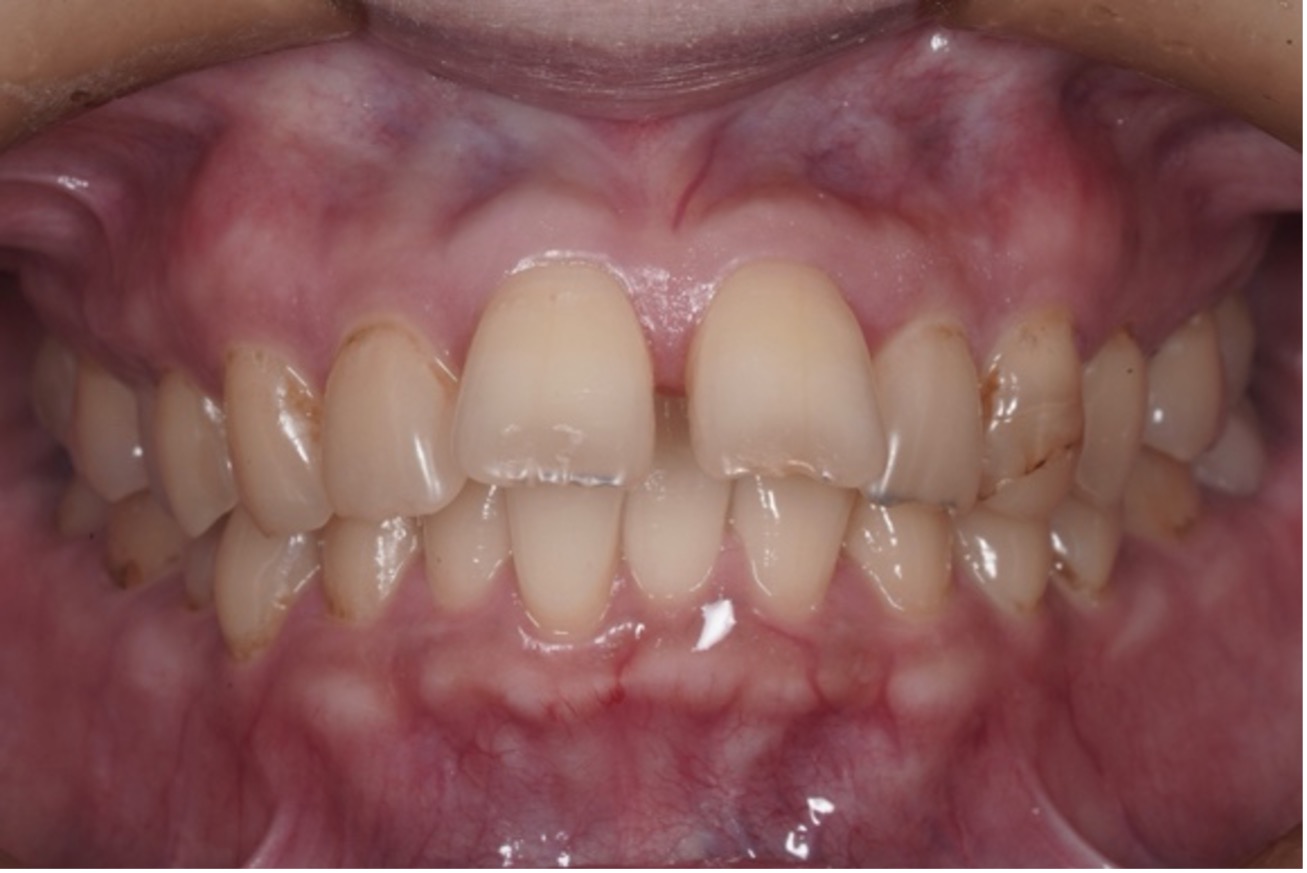

矯正治療の症例はこちら